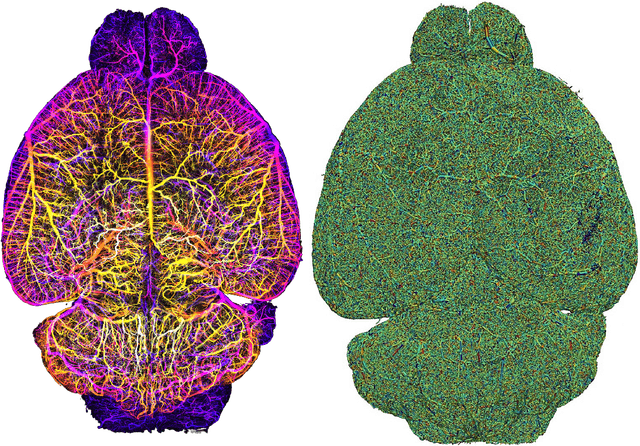

Abstract:Biological neural networks define the brain function and intelligence of humans and other mammals, and form ultra-large, spatial, structured graphs. Their neuronal organization is closely interconnected with the spatial organization of the brain's microvasculature, which supplies oxygen to the neurons and builds a complementary spatial graph. This vasculature (or the vessel structure) plays an important role in neuroscience; for example, the organization of (and changes to) vessel structure can represent early signs of various pathologies, e.g. Alzheimer's disease or stroke. Recently, advances in tissue clearing have enabled whole brain imaging and segmentation of the entirety of the mouse brain's vasculature. Building on these advances in imaging, we are presenting an extendable dataset of whole-brain vessel graphs based on specific imaging protocols. Specifically, we extract vascular graphs using a refined graph extraction scheme leveraging the volume rendering engine Voreen and provide them in an accessible and adaptable form through the OGB and PyTorch Geometric dataloaders. Moreover, we benchmark numerous state-of-the-art graph learning algorithms on the biologically relevant tasks of vessel prediction and vessel classification using the introduced vessel graph dataset. Our work paves a path towards advancing graph learning research into the field of neuroscience. Complementarily, the presented dataset raises challenging graph learning research questions for the machine learning community, in terms of incorporating biological priors into learning algorithms, or in scaling these algorithms to handle sparse,spatial graphs with millions of nodes and edges. All datasets and code are available for download at https://github.com/jocpae/VesselGraph .